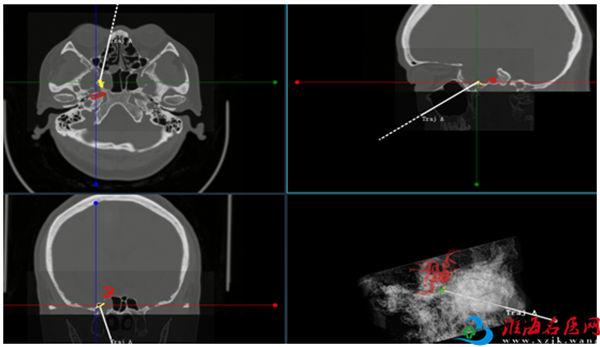

病因查明后,治疗就有了方向。经过积极治疗,L女士颅内感染症状得到控制,手术也排上日程。由于漏口位于蝶窦外侧隐窝,靠近颈内动脉,徐锋启动了鼻眼、鼻颅多学科会诊。专家组讨论后决定由神经外科和耳鼻咽喉科联合进行手术,利用神经导航微型手术机器人系统进行漏口的实时定位,经鼻微创入路在内镜下进行脑脊液鼻漏修补术,将手术创伤降至最低。

手术当天,在麻醉团队戴必照、卢思宇、孙媛媛和护理团队周慧、杨依心的密切配合下,徐锋和团队成员副主任医师张继东、主任医师朱保平,耳鼻咽喉科副主任、主任医师王浩联合为患者实施了手术,成功修补了漏口。